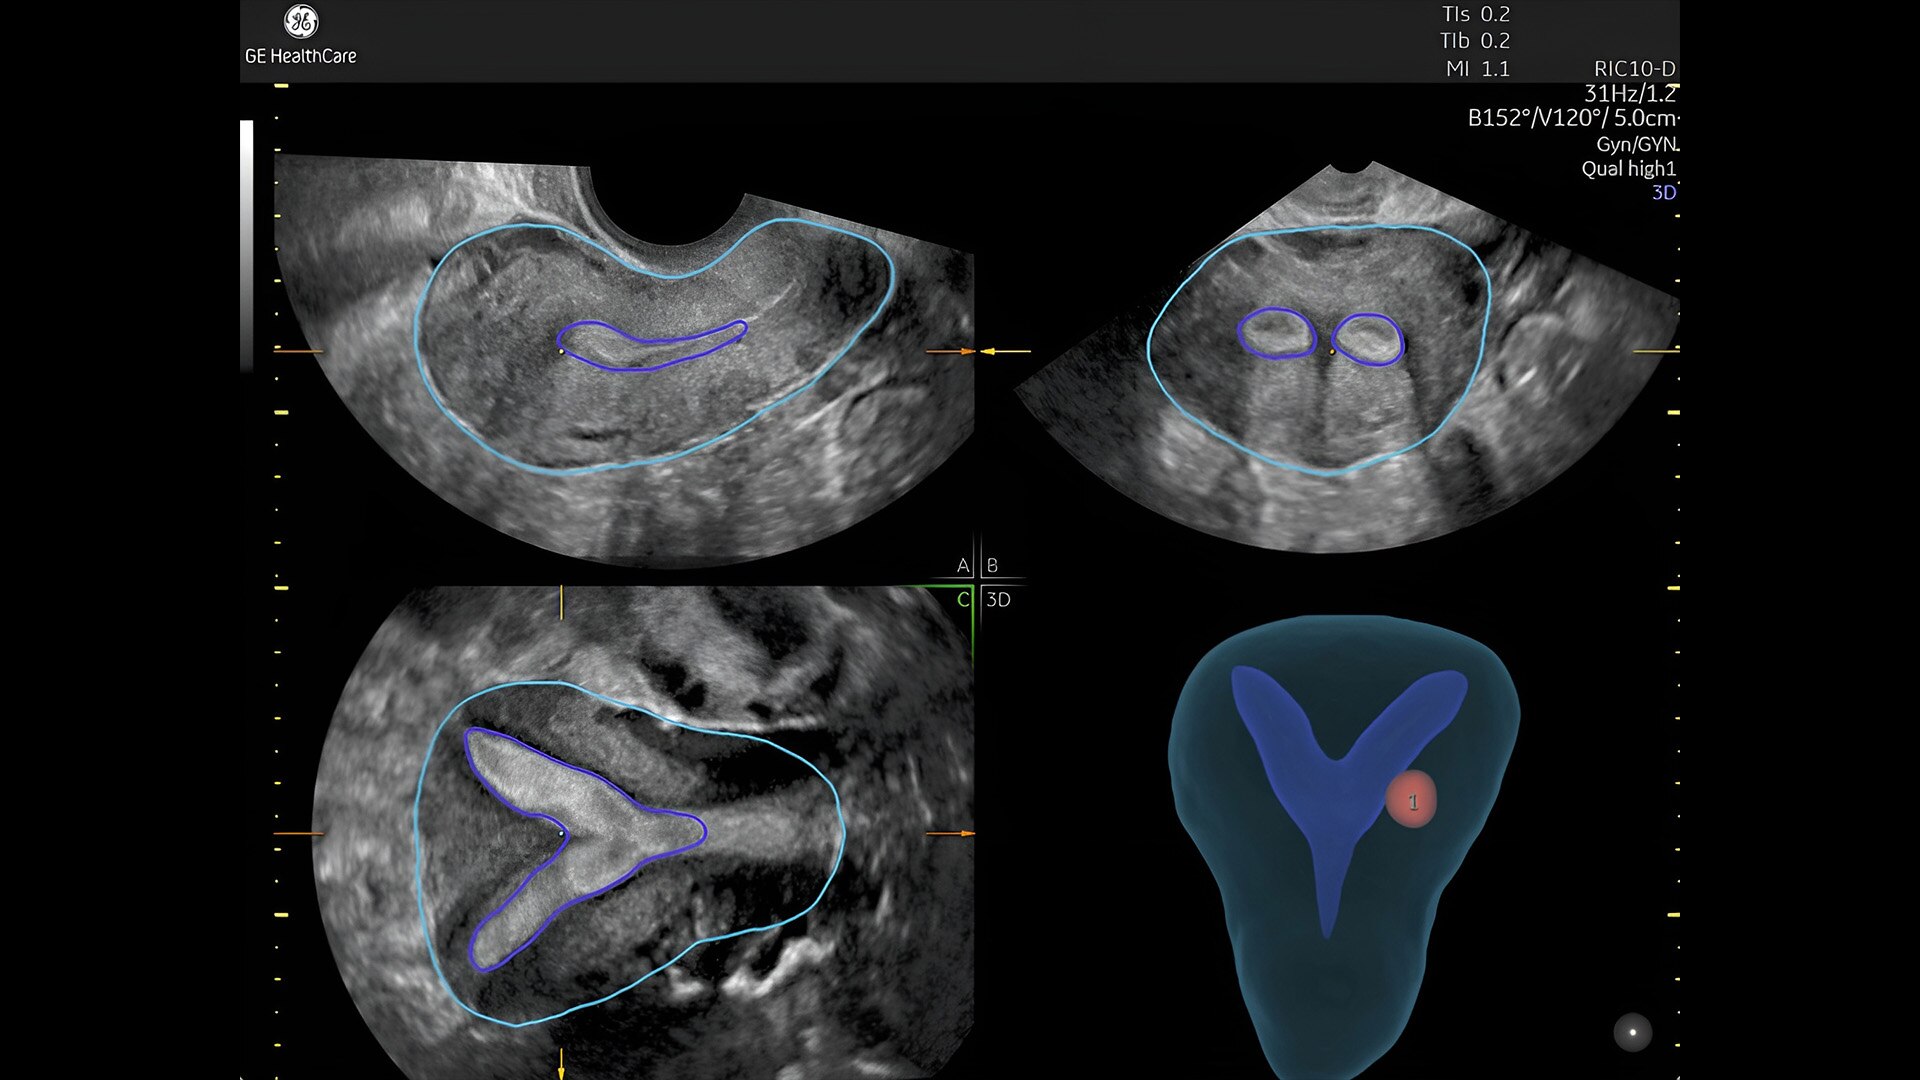

Pelvic health

Offer patient answers faster with Ai-based automation tools